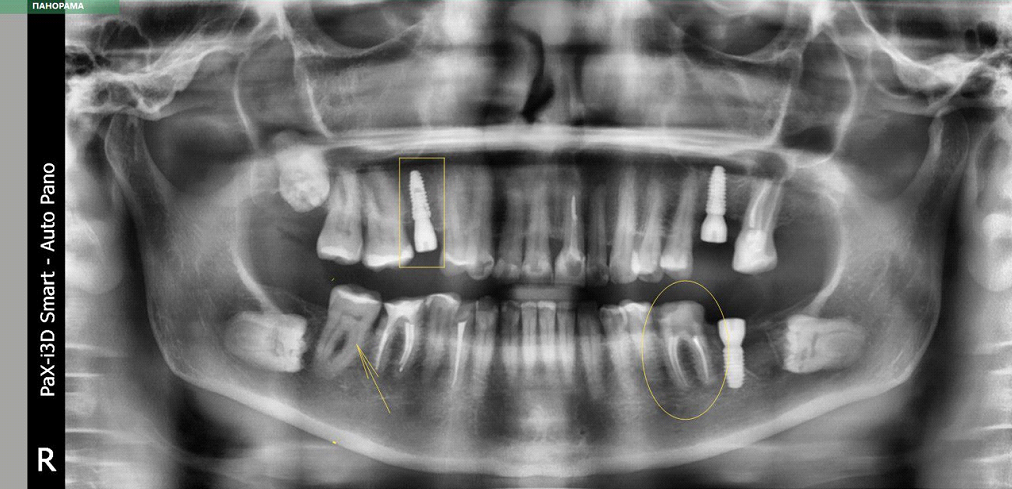

Фронтальная панорама (совмещение нескольких снимков). Прямоугольник — имплантат, его металл отражает излучение, но здесь включён постобработчик, который компенсирует гало-эффект. В овале зуб с пролеченными каналами, в каналах контрастный материал. Стрелка — зуб с живым нервом и пульпой.

Металлы, соответственно, дают очаги затемнения, как видите.